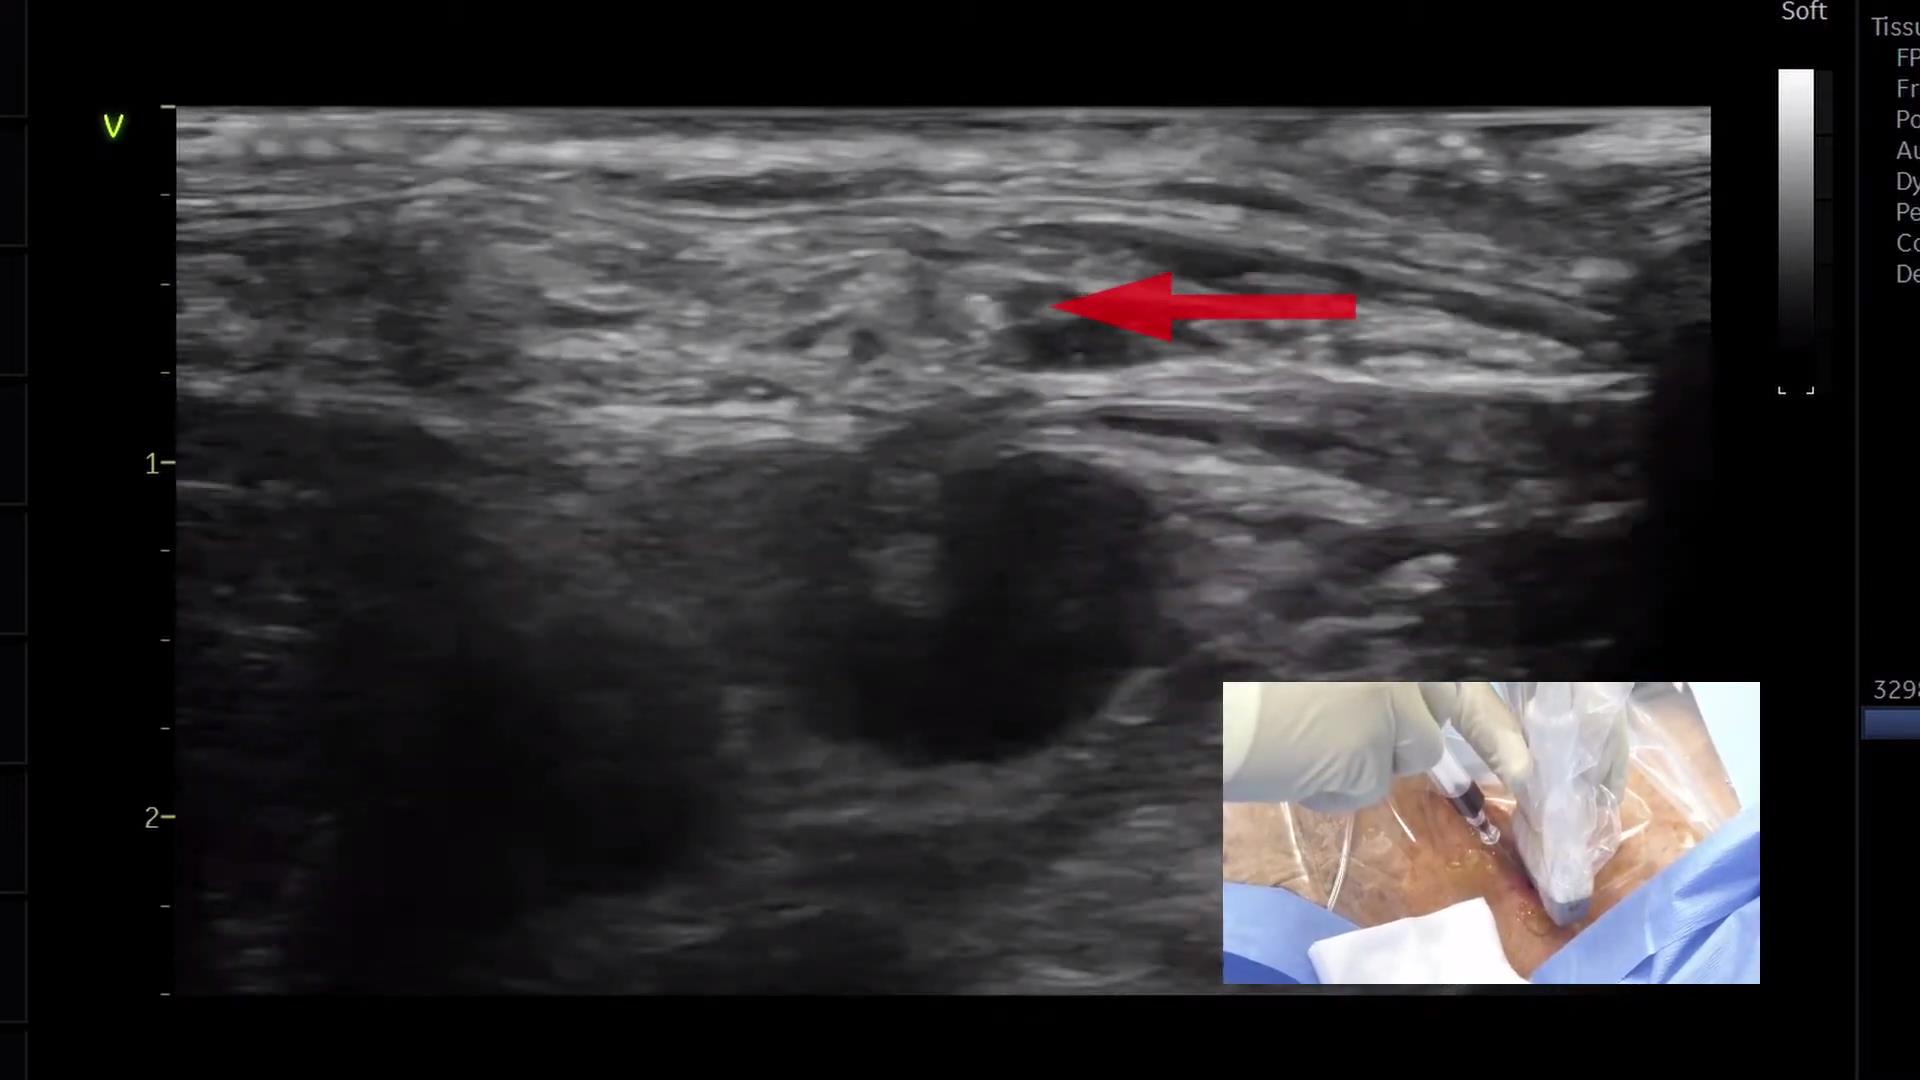

超声引导下锁骨下静脉穿刺置管

111 #锁骨下静脉穿刺